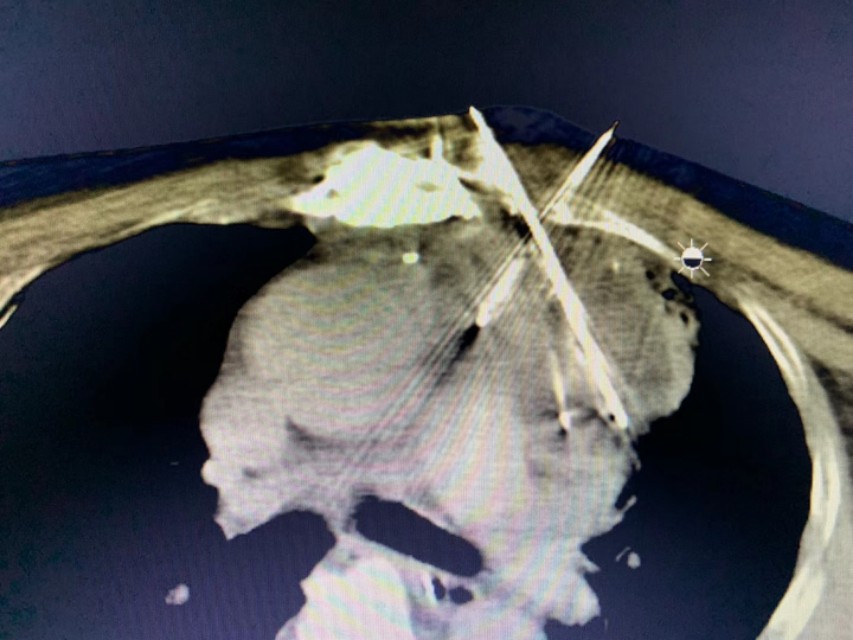

一位来自印尼患者,冠脉搭桥手术后患胸腺癌不适宜再手术,半年前已在我院行冷冻消融治疗,效果非常好。这次复查还有少许肿瘤残留,再次行冷冻消融治疗。

对不适宜手术的胸腺肿瘤,冷冻消融是一个非常好的选择。目前国际上发表的相关临床论文有四篇,分别是美国(25例)、日本(个案)、中国台湾(个案)、及中国!至今我院已经完成50多例的胸腺肿瘤冷冻消融,是国际上经验最多的医院之一。